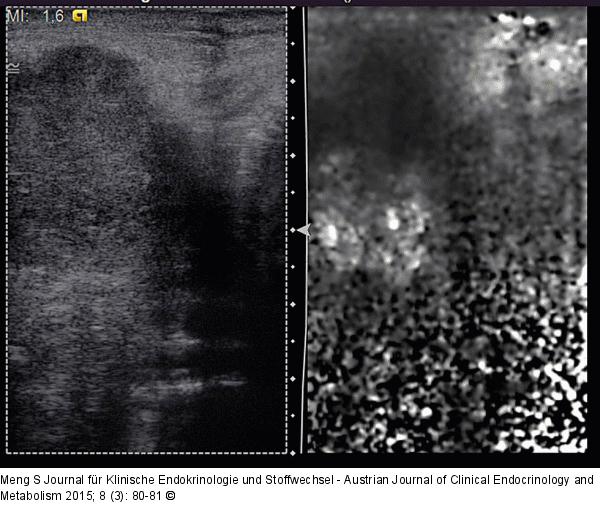

Abbildung 8: Lymphknoten-Elastographie Elastographie. Hier stellen sich beim gleichen Patienten wie in Abbildung 7 und gleichen Lymphknoten die harten Areale in der rechten Bildhälfte dunkel dar. Weiche Areale werden hell kodiert. Eine definierte mechanische Energie wird über den Ultraschallkristall eingebracht. |

Abbildung 8: Lymphknoten-Elastographie

Elastographie. Hier stellen sich beim gleichen Patienten wie in Abbildung 7 und gleichen Lymphknoten die harten Areale in der rechten Bildhälfte dunkel dar. Weiche Areale werden hell kodiert. Eine definierte mechanische Energie wird über den Ultraschallkristall eingebracht. |